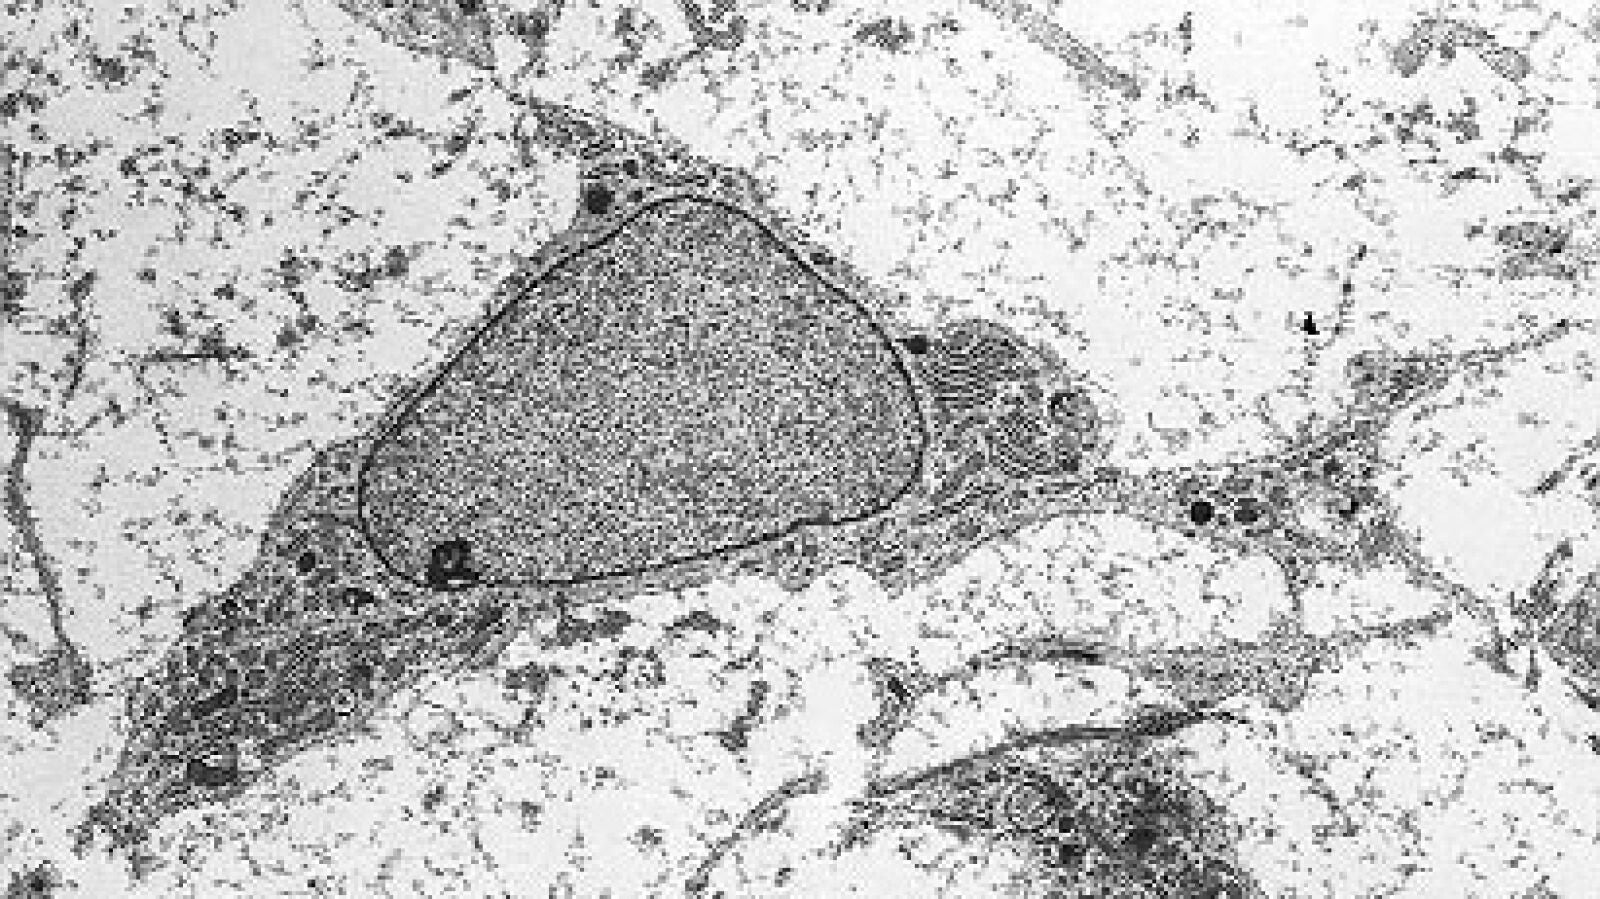

Estudios previos en animales y humanos habían sugerido el potencial de las células madre mesenquimales de la médula ósea, también conocidas como células estromales o MSC –por sus siglas en inglés– en el tratamiento del lupus, ya que se considera que la enfermedad puede ser producto de una alteración en el tejido mesenquimal, aquel que da lugar, por ejemplo, a huesos, músculos o cartílagos.

La terapia, consistente en la introducción por vía endovenosa de 90 millones de células madre mesenquimales, se administró cuando los pacientes se encontraban en momento de brote y no respondían al tratamiento previo. Después, se realizó seguimiento de los pacientes midiendo diferentes parámetros, específicos del riñón y generales, tras 1, 3, 6 y 9 meses del tratamiento.